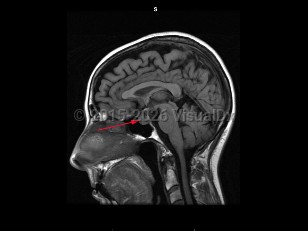

MeningiomaMeningioma

Pituitary tumor

CraniopharyngiomaCraniopharyngioma